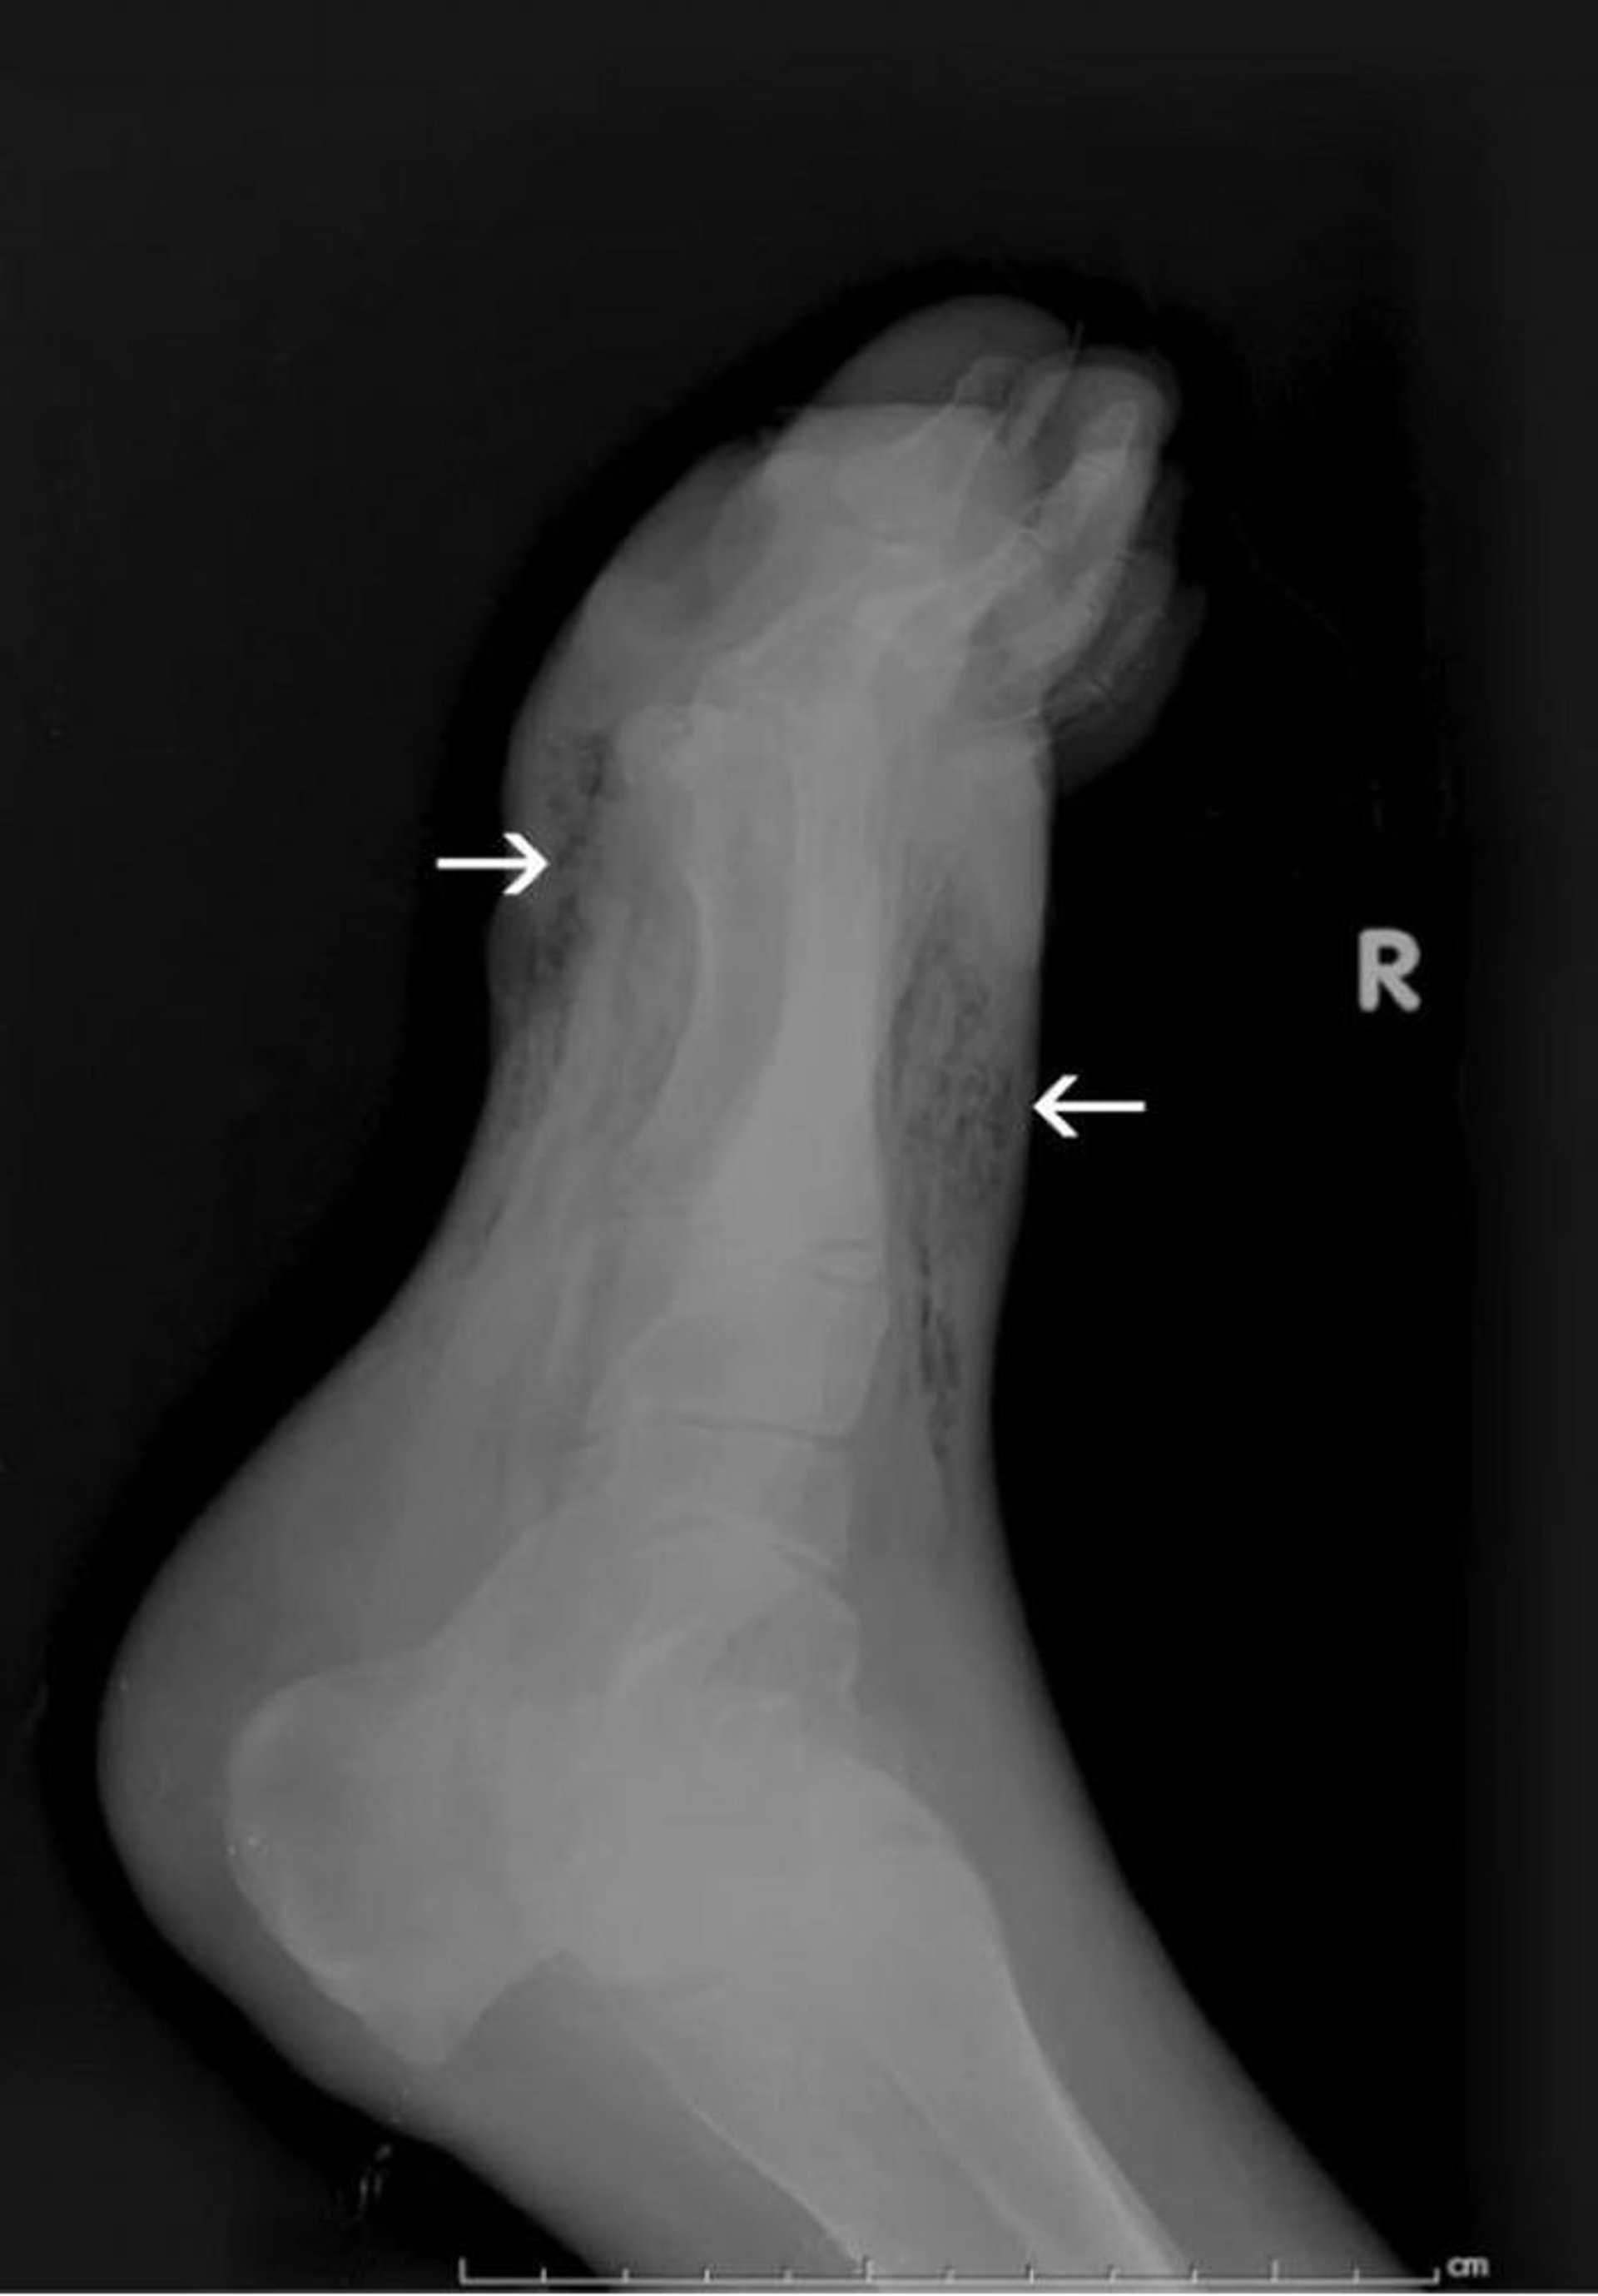

Gangrena del pie (radiografía)

Esta radiografía muestra gas en los tejidos blandos del pie (flechas).